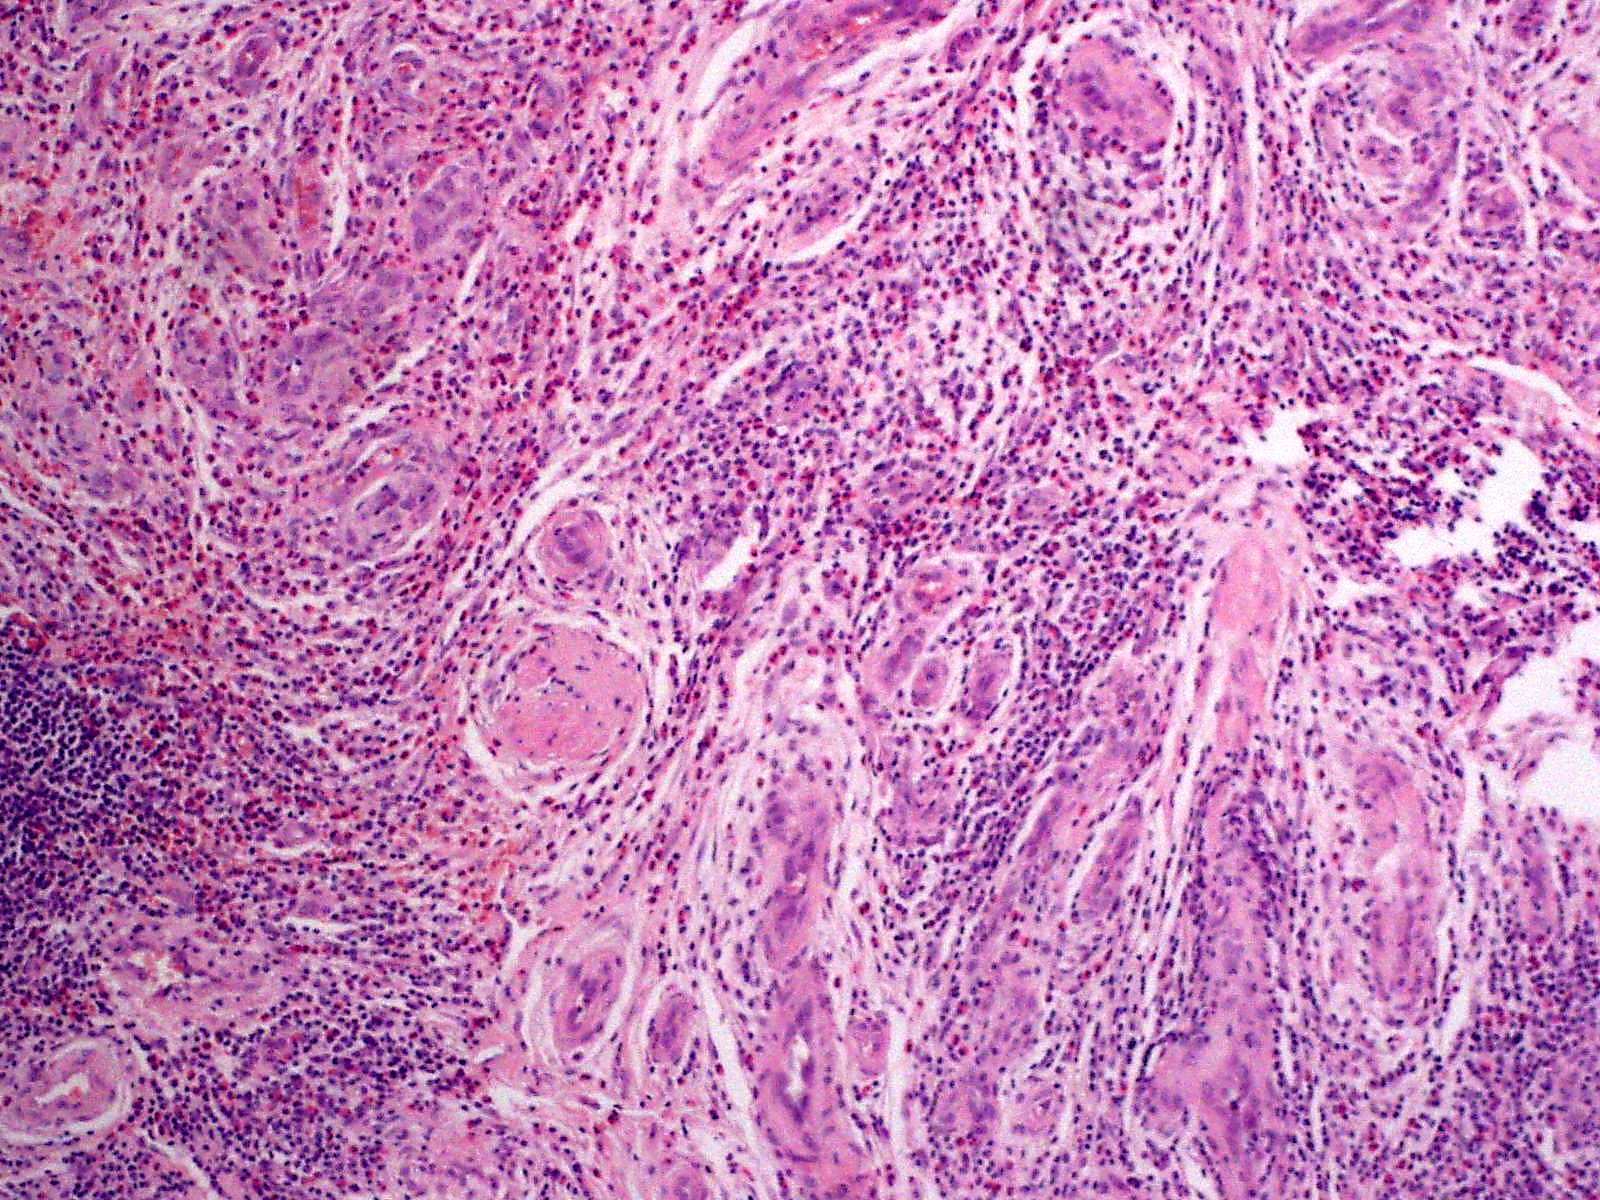

Histologie:

Uitgebreide proliferatie van dikwandige bloedvaten, met grote uitpuilende endotheelcellen (cobblestone appearance) met ovoïde nuclei en intracytoplasmatische vacuolen, altijd in combinatie met een perivasculair en interstitieel ontstekingsinfiltraat met daarin lymfocyten en veel eosinofiele granulocyten. Lymfoïde (folliculaire in de zin van lijkend op lymfeklieren) aggregaten komen voor. Angiolymphoid hyperplasia with eosinophilia is een benigne reactief proces, maar soms worden klonale T-cellen aangetroffen in het infiltraat, waardoor de vraag ontstaat of het mogelijk een voorstadium van een cutaan T-cel lymfoom zou kunnen zijn. Het beloop is echter benigne, en reactieve T-cel infiltraten kunnen monoklonaal zijn. De endotheelcellen zijn positief voor CD31, CD34, WT-1 (Wilms tumor-1) en VWF, en negatief voor keratine. De lymfocyten zijn vooral van het T-helper type, CD3, CD4, CD43, en CD45RO positief.

![Histologie van angiolymphoid hyperplasia with eosinophilia (click on photo to enlarge) [source: L. Wozniak en K.W. Zielinski - Wikimedia - Creative Commons Licnese 3.0] Angiolymphoid hyperplasia with eosinophilia](../../../images/angiolymphoid-hyperplasia-with-eosinophilia-2z.jpg) |

| ALHE (PA) |

PA foto:

L. Wozniak en K.W. Zielinski - Wikimedia (Creative Commons License

3.0).